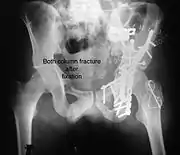

Both column fracture showing floating weight bearing dome

Both column fracture after fixation with screws and plates